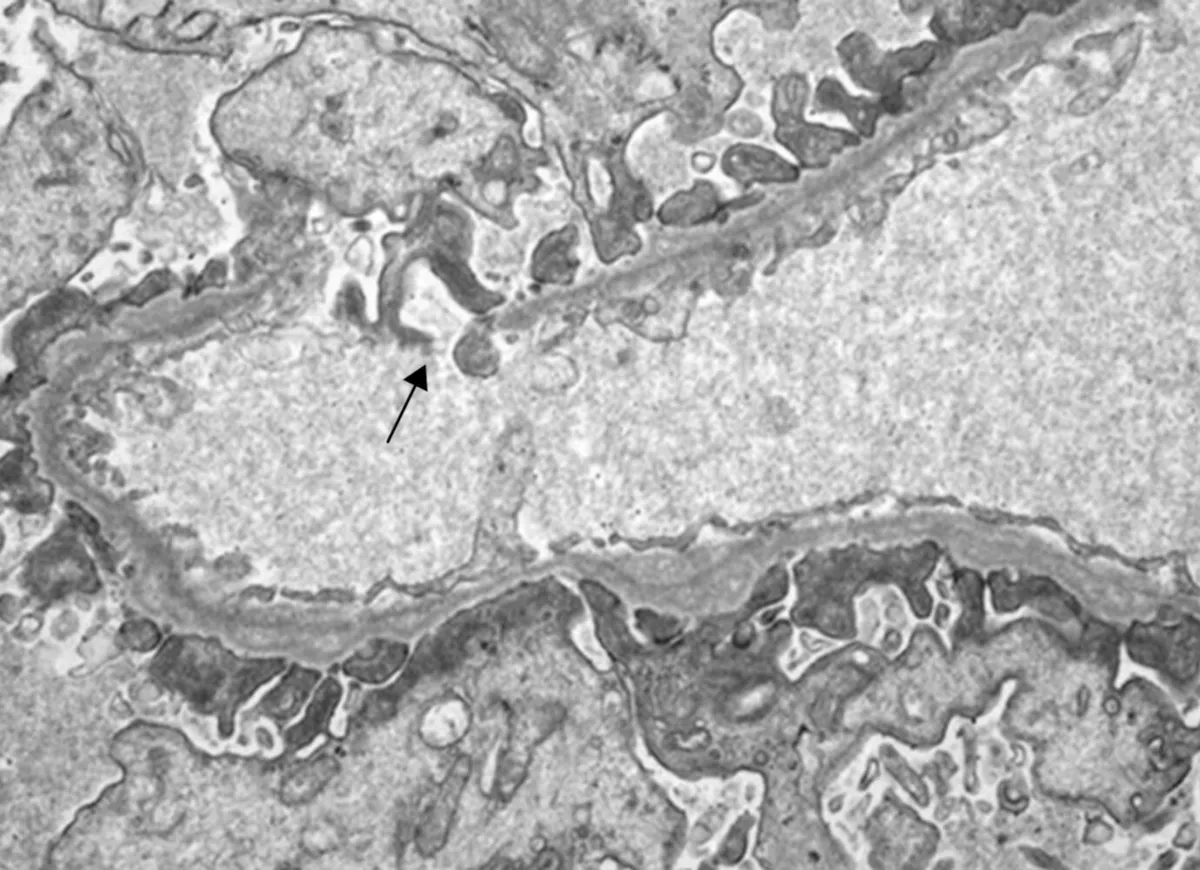

Injúria Renal Aguda (revisão Lancet 2025)

Injúria Renal Aguda (revisão Lancet 2025)